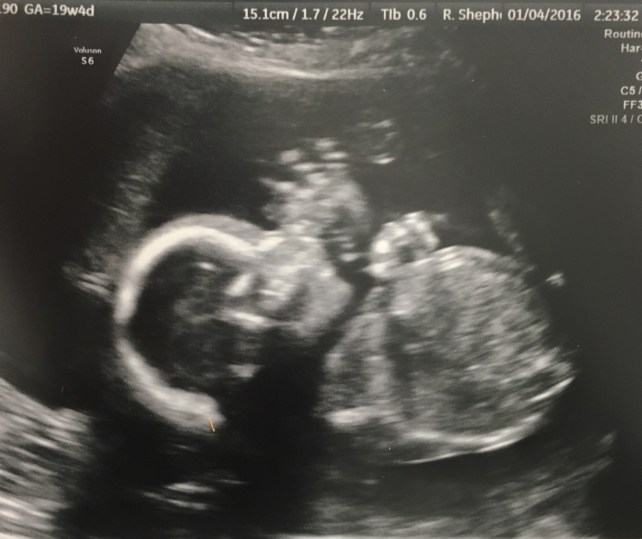

When I went to the doctor last time I had a sonogram and I got to really see him for the first time (my initial sonogram he was just too tiny). He is perfect. I got to see his brain, his spine, and his ribs. The technologist also showed me his heart and I got to see it beating as I listened to it. It was the most incredible experience. I even got a picture of him where it looks like he’s waving.

Hello World!